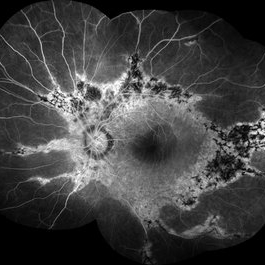

Gyrate Atrophy

Female patient, 28-year-old, with low vision in both eyes since childhood. In routine examination, important changes were observed with atrophic, symmetrical and bilateral aspects with apparently preservation of the central retina.

Condition/keywords: gyrate atrophy

Photographer: JEFFERSON R SOUSA - Study Center and Ophthalmological Research Dr. Andre M V Gomes, Institute Dr. Suel Abujamra São Paulo-Brazil

Imaging device: Topcon TRC-50 DX, Imaginet 5.0, angle de 50 graus. Flash 36 w-s